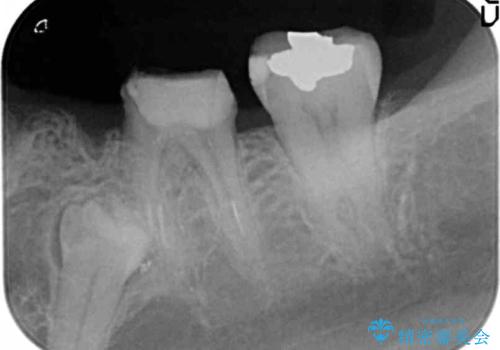

- 大人になってからも残っていた乳歯が揺れ始め、抜歯を覚悟しインプラント治療を希望して来院されました。

X線写真より、乳歯は抜歯が必要な状態でインプラントは小臼歯の埋伏により難しい状況であったのでブリッジによる補綴を選択しました。

ブリッジ治療の予知性を高めるために、虫歯の徹底的な除去に加え縁上歯質を確保するための歯周外科手術、マイクロスコープを用いた精密根管治療を行う治療計画としました。